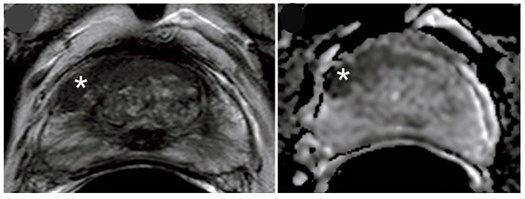

The highly-publicised PROMIS study shows that multi-parametric MRI can greatly improve the accuracy of prostate cancer diagnosis. MRI is a much less invasive test than a biopsy and doesn’t come with the risk of dangerous side effects such as infection. Should MRI be used to diagnose prostate cancer in Australia? The answer is not so simple.